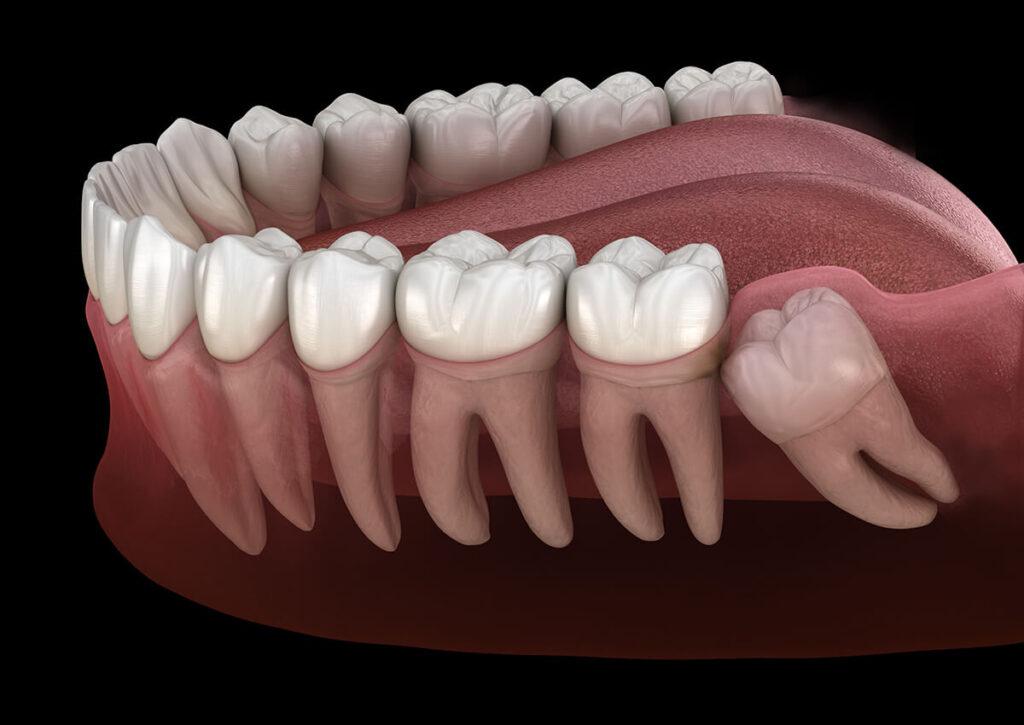

Extraction dent de sagesse

La chirurgie des dents de sagesse est l'extraction des dernières molaires pour prévenir ou traiter douleurs et infections. Elle se fait sous anesthésie, avec une récupération variable selon la complexité de l'intervention.